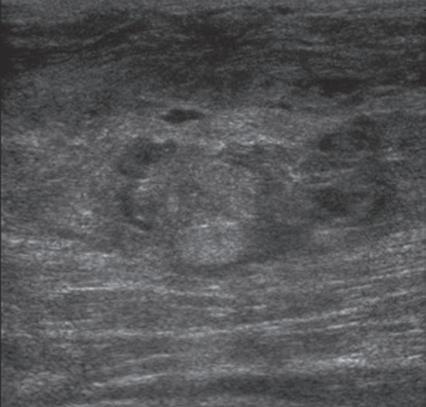

labrum of the hip and shoulder, and the knee menisci are hyperechoic (Fig. 1.7B). Ligaments have a hyperechoic, striated appearance that is more compact compared with tendons (Fig. 1.8). In addition, ligaments are also identified in that they connect two osseous structures. Often normal ligaments may appear relatively hypoechoic when surrounded by hyperechoic subcutaneous fat; however, a compact linear hyperechoic ligament can be appreciated when imaged in long axis perpendicular to the ultrasound beam. Normal peripheral nerves have a fascicular appearance in which the individual nerve fascicles are hypoechoic, surrounded by hyperechoic connective tissue epineurium (Fig. 1.9).4 Hyperechoic fat is typically seen around larger peripheral nerves.

In short axis, peripheral nerves display a honeycomb or speckled appearance, which assists in their identification. Because peripheral nerves have a relatively mixed hyperechoic and hypoechoic echotexture, their appearance changes relative to the adjacent tissues. For example, the median nerve in the forearm, when surrounded by hypoechoic muscle, appears relatively hyperechoic; in contrast, more distally in the carpal tunnel, when it is surrounded by hyperechoic tendon, the median nerve appears relatively hypoechoic (see Fig. 5.4D). The epidermis and dermis collectively appear hyperechoic, whereas the hypodermis shows hypoechoic fat and hyperechoic fibrous septa (see Fig. 1.7).